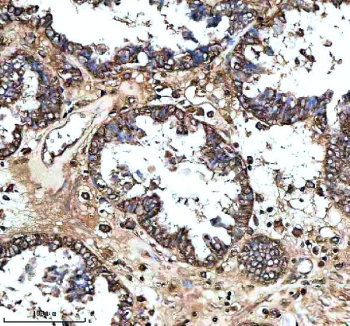

Immunohistochemical staining of MS4A4E using anti-MS4A4E antibody. MS4A4E was detected in a paraffin-embedded section of human prostate cancer tissue. Heat mediated antigen retrieval was performed in EDTA buffer (pH 8.0, epitope retrieval solution). The tissue section was blocked with 10% goat serum. The tissue section was then incubated with 2 ug/ml rabbit anti-MS4A4E antibody overnight at 4oC. Peroxidase Conjugated Goat Anti-rabbit IgG was used as secondary antibody and incubated for 30 minutes at 37oC. The tissue section was developed using an HRP secondary and DAB substrate.